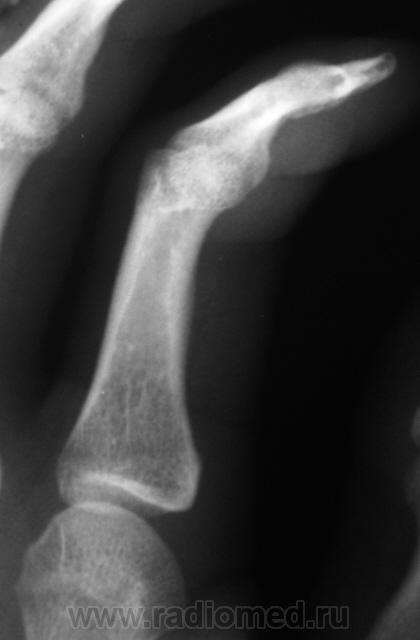

Травма. Пациент направлен на рентгенографию 2 пальца.

Валентин Львович, вы ж укажите, где локальная болезненность. Может перелом основания осн. фаланги?

Участок максимальной болезненности.

??? Головка ср.ф. какая-то скошенная, но деструктивн. изм., повреждений не вижу.

Меня тоже смутила форма головки фаланги.